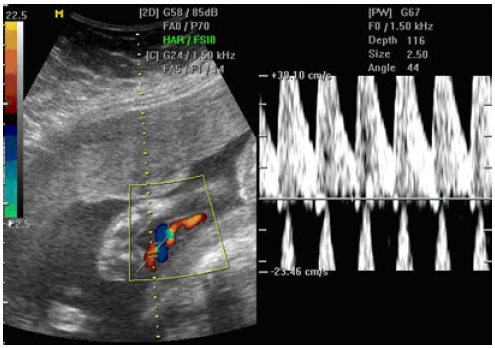

Qual a informação mais aceita sobre as varicoceles